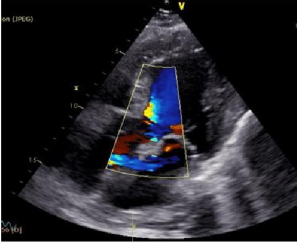

Mrs X, a 26-year-old Muslim lady from Dhaka Bangladesh presented to us with the complaints of fever, palpitation and weight loss for last 3 months. According to the statement of the patient, she was reasonably well 3 months back. Then she developed fever which was low grade, intermittent in nature, and the highest recorded temperature was 100°F. Fever was not associated with chills and rigors and there was no history of evening rise of temperature or night sweat. For the last 3 months, she developed palpitations which was gradual in onset, aggravated after exertion and persisted even at rest. It was not associated with any chest pain, shortness of breath, dizziness or syncope. On query, she gave history of bilateral upper limb pain for 3 months, especially in both the forearm and hand, which was gradual in onset, aching in nature, non-radiating, present most of the time, and aggravated by doing any kind of work, like combing, dishwashing and relieved by rest. She also complained about anorexia, and she mentioned that she lost 10 kg of weight in 3 months which was unintentional. She denied any cough, joint pain, oral ulcer, discoloration of fingers on cold exposure, skin rash, abdominal pain, headache, convulsion, miscarriage and bleeding from any site. Her bowel and bladder habits were normal. With these complaints she sought multiple medical consultations and extensive primary investigations. On the basis of a positive MT test (22mm) she was started on anti-TB from outside 9 days back without minimal improvement. She had no significant past history of illness. She was non-smoker and she was nonalcoholic. She had no known exposure to TB patients. She practices safe sexual intercourse and was BCG vaccinated. On examination, she was mildly anemic, BMI was 17.31 kg/m2, temperature 100o F, clubbing- absent. Blood pressure 140/90 mmHg in right arm and 110/70 mm Hg in Left arm. All the peripheral pulses were present but of low volume. Visible pulsation is seen in the right carotid area. There was no ulcer, no skin rash but there was induration over the volar aspect of left forearm. Thyroid gland was not enlarged, and no lymph nodes were palpable. On cardiovascular system examination, dancing carotid pulse was seen in right carotid area (Corrigan sign). Apex beat was present in the left 5th intercostal space, shifted laterally, 10 cm from the midline and forceful in nature. There was no palpable P2 or A2. No tenderness was found in the carotid area. First and second heart sounds are normal in all cardiac areas. There is high pitched, blowing early diastolic murmur in the left lower parasternal area, best heard with the patient sitting and bending forward and breath hold after expiration. Other systemic examination revealed no abnormalities. On investigation, complete blood count revealed normocytic, normochromic anemia with hemoglobin 9.2 gm%. White blood cells and platelet counts were within normal limit. ESR and CRP were raised to 126 mm in the first hour and 39 gm/L respectively. Liver function tests, renal function tests and thyroid function tests failed to reveal any abnormalities. ASO titer, LDH, s. uric acid, urine routine examination, ultrasonography of whole abdomen were normal. Vasculitis screening with ANA, Anti CCP, P-ANCA, C- ANCA were nonconclusive. TPHA, blood culture, 2 samples drawn from 2 different sites were negative. Chest X-ray PA view showing mediastinal widening (Figure 1). Ct chest failed to reveal any mediastinal lymphadenopathy or lung parenchymal lesion. Color doppler echocardiography revealed dilated aortic root with moderate to severe aortic regurgitation with no evidence of vegetations or thrombus and no regional motion wall abnormalities with good left ventricular systolic function (LVEF 64%) (Figure 2)

Figure 2: Coloe doppler echocardiography showing moderate to severe aortic regurgitation.